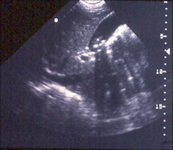

Ultrassonografia de vesícula biliar demonstrando colelitíase com sombreamento característico

Do acervo de Dr. KuoJen Tsao; usado com permissão